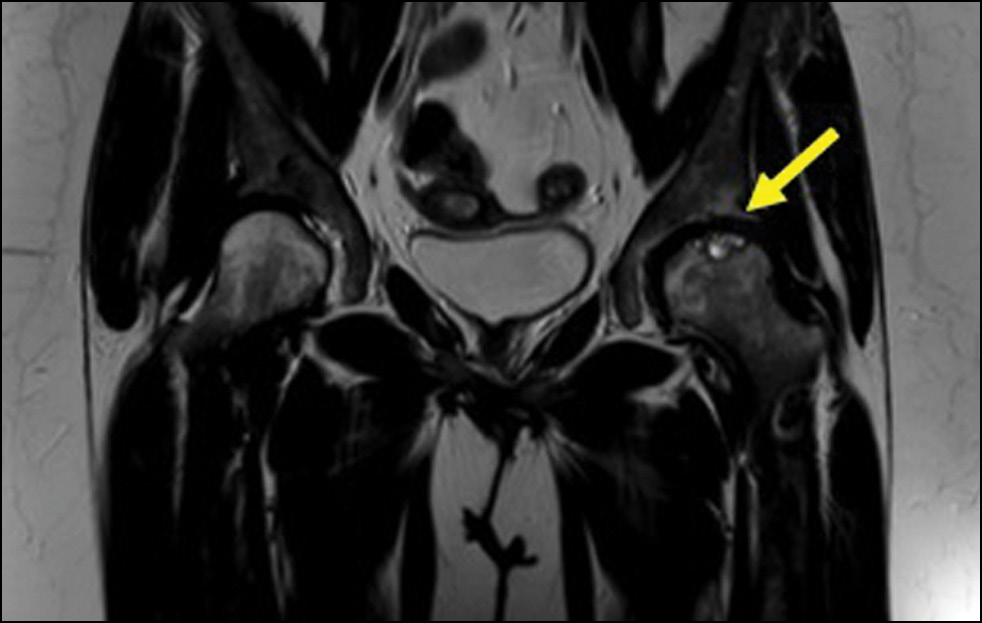

Из 251 пациента у 75 (30%) выявлено наличие АНГБК, причём у 17 — с двух сторон. Из этих 92 случаев АНГБК в 35 (38%) не наблюдали деформацию головки бедра и развитие вторичного коксартроза. Изменения были выявлены на МРТ и рентгенограммах при первичном обследовании пациентов, а участки остеонекроза соответствовали типам 2 и 3А по классификации ARCO с размером менее 15% поверхности (рис. 1). В динамике при контрольных МРТ-исследованиях не было отмечено увеличение размеров выявленных ранее очагов. В остальных 57 случаях наблюдалась деформация головки бедренной кости, причём клиническая и рентгенологическая картина значительно различалась у пациентов с дебютом АНГБК в детстве (11 больных) и взрослом возрасте (46 больных).

Рис. 1. МРТ тазобедренных суставов (Т2-взвешенное изображение, корональная проекция). II стадия кортикомедуллярного остеонекроза головки левой бедренной кости (симптом двойной линии), тип 2А по классификации АRCO.

Fig. 1. MRI of the hip joints (T2-WI, coronal projection). Stage II corticomedullary osteonecrosis of the left femoral head (double line symptom), type 2A to ARCO classification.